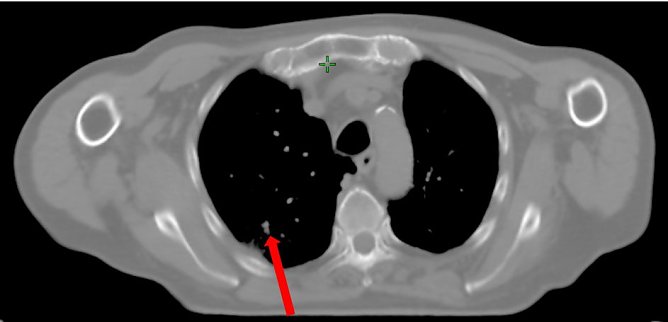

Bei einem Patienten im Nordhäuser Klinikum mit Lungenkrebs wurde diese neue Methode der Bestrahlung bereits erfolgreich angewendet. Der Tumor in der Lunge des Mannes wurde mit einer fünfmal höheren Dosis als normal bestrahlt, dabei lag die Zeit der Bestrahlung nur unwesentlich höher im Vergleich zur normalen Zeit von zwei bis drei Minuten. Für den Patienten ist das alles völlig schmerzfrei.

Nun soll diese Form der Therapie verstärkt bei Patienten angewendet werden, die aus verschiedensten Gründen nicht operabel sind oder die eine Operation ablehnen.